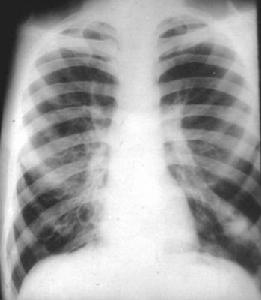

2.X線胸片 可無異常(占10%)或肺紋理增多、增粗,排列紊亂囊狀支氣管擴張在胸片上可見粗亂肺紋理中有多個不規則蜂窩狀(捲髮狀)陰影,或圓形、卵圓形透明區,甚至出現小液平,多見於肺底或肺門附近。柱狀支氣管擴張常表現為“軌道征”,即在增多紋理中出現2條平行的線狀陰影(中央透明的管狀影)